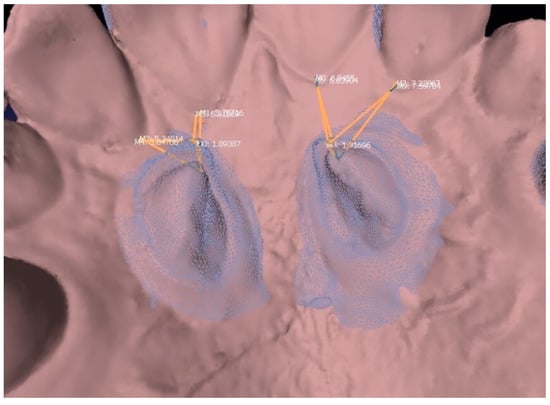

- canine eruption at T1 and T2,

- maximum length of the vestibular surface at T1 and T2,

- maximum length of the palatal surface at T1 and T2,

- distance between canine and central incisor at T1 and T2,

- distance between canine and lateral incisor at T1 and T2.

- maximum length of the palatal and vestibular surface at T1 and T2,

- distance of the cusp from the zenith of central incisor and lateral incisor at T1 and T2,

- the eruption at T1 and T2 (the eruption can’t be calculated in a realistic way, but only by measuring the approximate height between the cusp and the palatal mucosa).